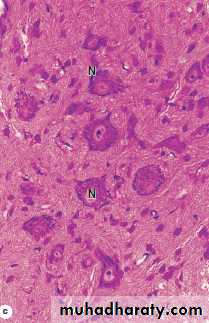

Spinal cord

Spinal cord grey matter